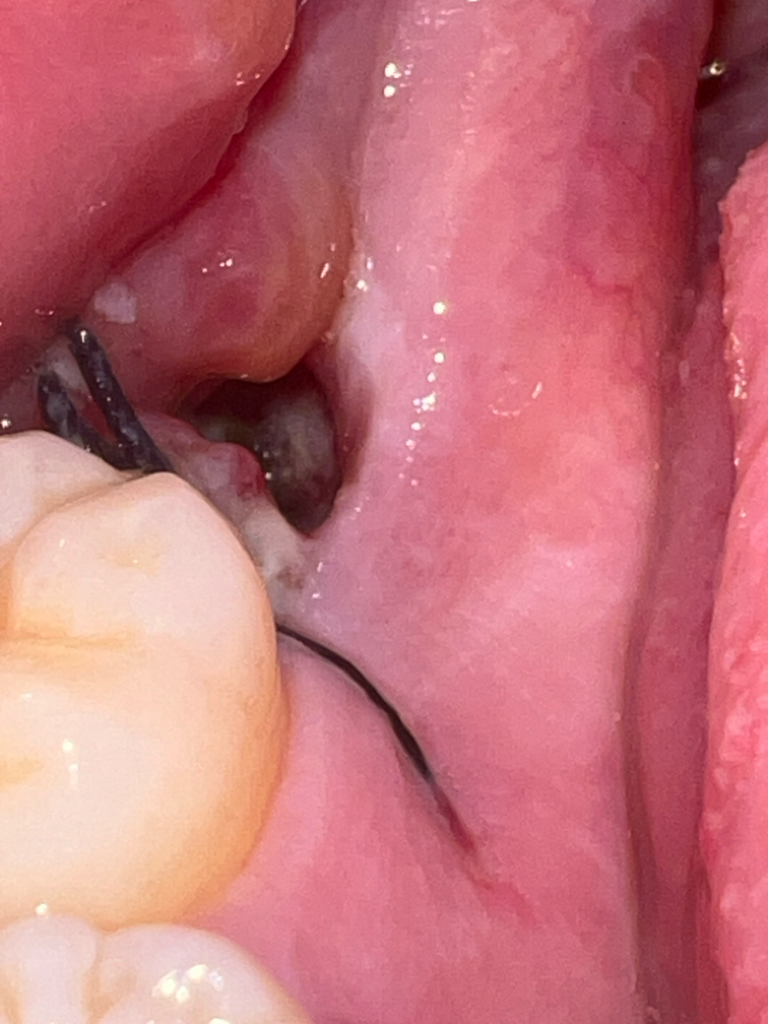

사랑니를 발치 하고 발치한 부위를 오늘 확인 하였더니 구멍에 흰색? 누런색 무언가가 보입니다 혹시 드라이 소캣일까요?

또 지금 사랑니 발치로 인해 옆에 잇몸과 함께 꼬맨부분이 더 아픈데 정상일까요??

• 2번 째 사진

현재 드라이소켓은 아닌 혈병으로 보이며 아무는 과정의 자연스런 현상입니다. 발치후 주변잇몸에 통증이 나타나는 경우 있으며 통증이 심한 경우 소염진통제 복용을 권합니다.

회복 과정에서 하얗게 막이 생기는 것은 정상적인 반응입니다. 극심한 통증이나 냄새가 나면 치과를 가보시는 게 좋습니다.